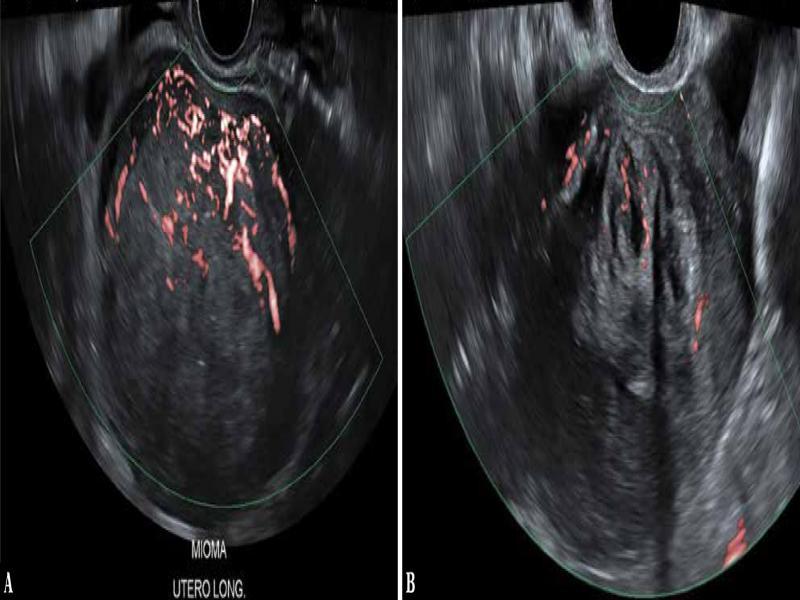

Fig. 2.